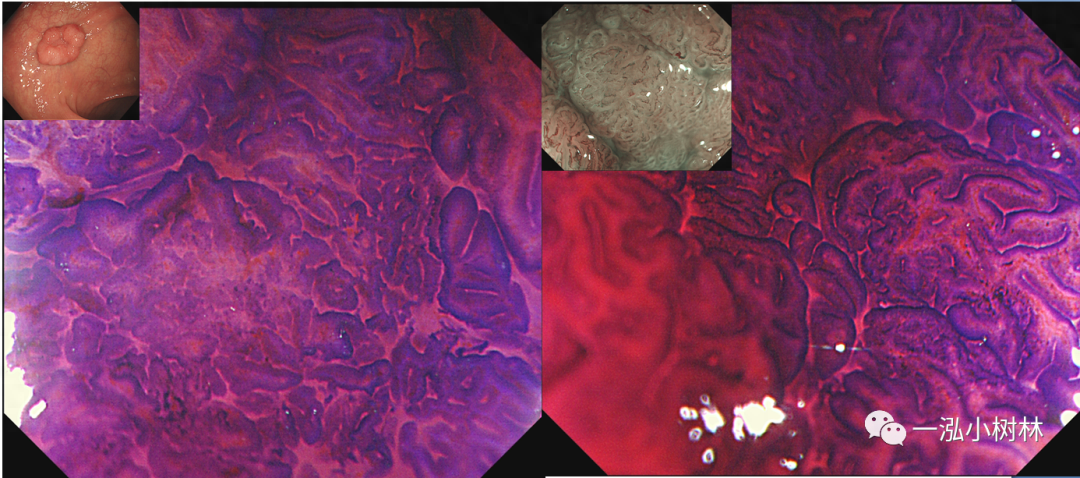

图21 结肠管状绒毛腺瘤(Pit Pattern IV型)

图30 结肠管状绒毛腺瘤 HGIN (Pit Pattern IV-VI型)